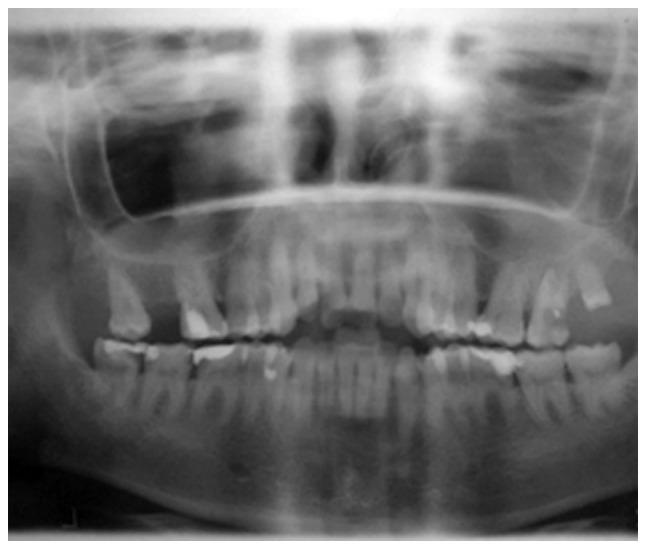

There are numerous types of sinusitis caused by fungal strains, some of which already colonize the nasal cavity. Mild forms present fungus balls growing inside a preexisting sinus cavity. The invasive type ranges from chronic manifestations to acute aggravated episodes. The latter scenario is encountered in cases with reduced immune responses, such as patients with diabetes, individuals receiving any form of transplant, AIDS cases and chemotherapy patients. Without the control of immunosuppression, the infection is aggravated and extends to the orbit and inside the skull base, regardless of the prompt surgical and medical treatment. This is the most common pathogenic fungus on the nasal sinuses level. It can occasionally enter the sinus cavity during dental procedures. The pathogenesis is enhanced by anaerobic conditions in poorly ventilated sinus cavities. Rhinosinusal aspergilloma has a slow, insidious evolution over months and even years. Our experience revealed the presence of both a dental problem and previous self-administered antibiotic regimens in almost every case. The initial symptoms are common with sinusitis of dental origin, but aspergilloma should be considered when a patient with a competent immune system does not respond to standard antibiotic treatment. The final diagnosis of rhinosinusal aspergilloma is conducted on a pathology sample with silver staining. The bacteriology exam of the sinus secretion rarely reveals a fungus infection; however, as revealed in our clinical experience, there may be coinfection with other multidrug-resistant bacteria. Surgical treatment must establish a wide exposure of the sinus cavity and correct drainage regardless of the external, combined or endoscopic approach. Early diagnosis and emergency surgical debridement along with administering systemic antifungal compounds in some cases represent the key to the successful treatment of invasive aspergilloma.

由真菌菌株引起的鼻窦炎有多种类型,其中一些已经在鼻腔定植。轻度形式表现为在已有的鼻窦腔内生长真菌球。侵袭性类型从慢性表现到急性加重发作不等。后一种情况见于免疫反应降低的病例,如糖尿病患者、接受任何形式移植的个体、艾滋病患者和化疗患者。如果不控制免疫抑制,无论进行及时的手术和药物治疗,感染都会加重并蔓延至眼眶和颅底。这是鼻窦层面最常见的致病真菌。它偶尔会在牙科手术过程中进入鼻窦腔。通风不良的鼻窦腔内的厌氧条件会增强其发病机制。鼻窦曲霉菌瘤在数月甚至数年的时间里缓慢、隐匿地发展。我们的经验表明,几乎每个病例都存在牙齿问题和先前自行使用抗生素的情况。初始症状与牙源性鼻窦炎常见症状相同,但当免疫系统正常的患者对标准抗生素治疗无反应时,应考虑曲霉菌瘤。鼻窦曲霉菌瘤的最终诊断通过银染色的病理样本进行。鼻窦分泌物的细菌学检查很少能发现真菌感染;然而,正如我们的临床经验所示,可能会合并其他多重耐药菌感染。无论采用外部、联合还是内镜方法,手术治疗都必须广泛暴露鼻窦腔并建立正确引流。早期诊断、紧急手术清创以及在某些情况下使用全身性抗真菌药物是侵袭性曲霉菌瘤成功治疗的关键。